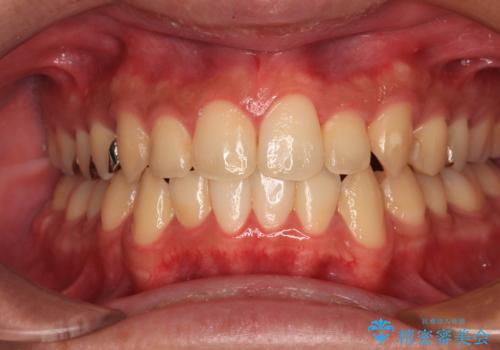

- くちばしのような前歯の突出感を気にして来院された患者様です。

上下左右第一小臼歯4本を抜歯して、積極的に口元を引っ込めるよう、ワイヤー装置にて矯正治療を行うこととしました。